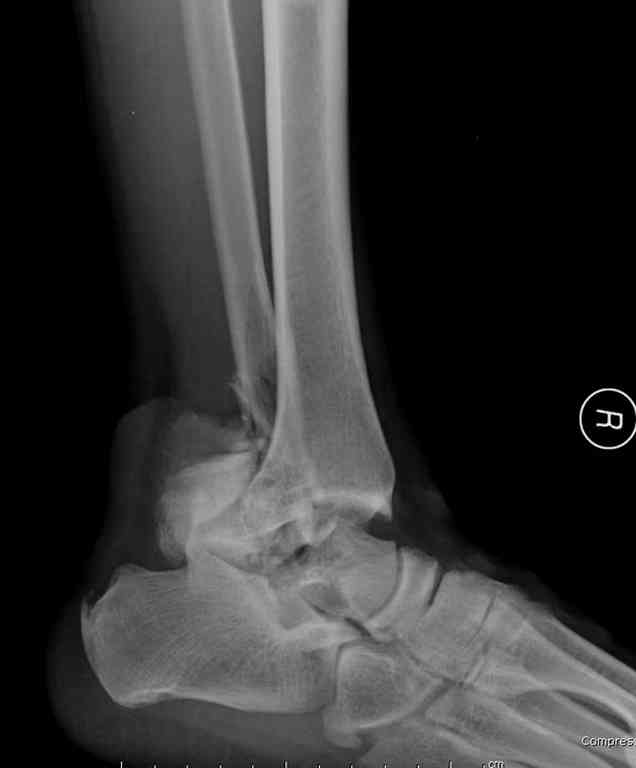

Второй случай прооперирован вчера.

10 дней назад поступил с открытым повреждением медиальной лодыжки и переломо вывихом таранной кости. Ургентно сделана репозиция с наложением наружного фиксатора + Irrigation&Debridment.

Во время репозиции выявили повреждение заднего сухожилия м. тибиалис и задней большеберцовой артерии. Медиальную рану удалось закрыть частично и установлен вакуум.

Дважды провели Irrigation&Debridment с заменой вакуума.

Вчера провели фиксацию.